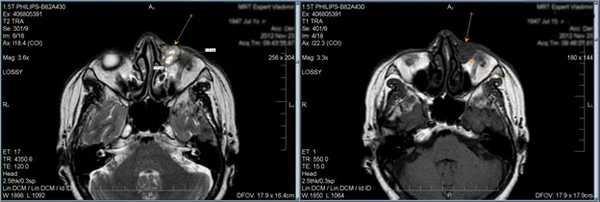

2. Синдром Толоза-Ханта (болезненная офтальмоплегия, синдром верхней глазничной щели)

Характеризуется вовлечением в процесс всех структур, проходящих через верхнюю глазничную щель (артерия, вена, отводящий нерв, блоковый нерв и глазодвигательный нерв, первая ветвь тройничного нерва), и прилегающего к ней кавернозного синуса. Субъективные проявления cиндрома Толоза-Ханта: болезненность в области орбиты, двоение в глазах, экзофтальм и хемоз.

Тот же пациент, исследование в динамике через 4,5 года

Исследование в 2008 году Исследование в 2013 году